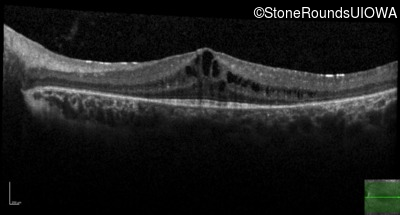

Age at visit: 7 years (Visit 2)

Age at visit: 8 years